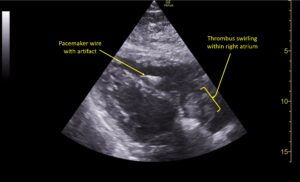

Wolff A, et al. Right atrial thrombosis. Parasternal long US 3, annotated

Wolff A et al. Right atrial thrombosis. Parasternal long US 3 annotated